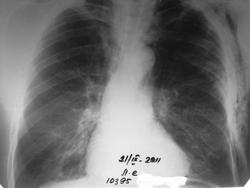

перелом ребер слева, обширная подкожная и межмышечная эмфизема. логически должен быть пневмоторакс(клинически дыхание прослеживается во всех отделах) видится мне пневмомедиастинум. Как Вам уважаемые коллеги?

Если переломы рёбер не вызвали пневмоторакс, значит подкожная эмфизема грудной клетки появилась в результате пневмомедиастинума. А такое количество воздуха мимо лёгких может быть при разрыве трахеи или главных бронхов. Нужно делать бронхоскопию, Александр Викторович.

А вариант малого пневмоторакса, который не виден за эмфиземой мягких тканей? По снимку максимальная эмфизема в области травмы, так что повреждение трахеи и крупных бронхов не особо вероятно, ИМХО. Но итог радует в любом случае - выписка .

Не пойму, о чем спор? Перелом рёбер ⇒ повреждение легочной паренхимы отломком ребра ⇒ пневмоторакс и эмфизема мягких тканей в области травмы с распространением воздуха краниально при вертикальном положении пациента. Тут вопросов нет?)) За подкожной эмфиземой не проблема увидеть край висцеральной плевры. Гораздо сложнее разглядеть его при межмышечной эмфиземе, как в данном случае. А уж оценка легочного рисунка на фоне воздуха в мышцах - вообще высший пилотаж!

Пневмомедиастинум возникает по ряду причин, не только при разрыве бронхов и трахеи. Оставив в стороне ятрогению, остановлюсь на травматическом механизме. Чаще по рентгенограммам проходят незамеченными переломы грудины (передняя медиастинальная плевра) без видимого смещения и головок/шеек ребер без видимого смещения (задняя). Откройте анатомический атлас и посмотрите границы медиастинальной плевры: до 12 ребра сзади и до 6 ребра спереди. Места для проникновения воздуха в средостение при открытом повреждении вдоль границ передней и задней медиастинальной плевры - ой, как много. Кто-то будет спорить, что в приведенном случае открытая травма? Повреждение проникающее, и допустив, что имеется повреждение грудины или 1 и более головок ребер, нетрудно представить и повреждение медиастинальной плевры, и проникновение воздуха в средостение.

Есть механизм пневмоторакса и пневмомедиастинума и без переломов ребер - при баротравме происходит разрыв терминальных (субплевральных) альвеол. "Хорошее" сотрясение грудной клетки с переломом ребер или без оного вполне может сопровождаться таким разрывом терминальных альвеол, в результате чего воздух из альвеол попадает в плевральную полость и/или перибронхиально попадает в средостение по градиенту давления (давление в средостении ниже, чем воздуха в альфеолах).

То, что кто-то видит край плевры, кто-то не видит, - чисто субъективно. На мой взгляд, факт эмфиземы мягких тканей, переломов, пневмомедиастинума в случае Саши - неоспорим. А пневмоторакс... так стоит же дренаж, так что - последующий Rg-контроль и визуализация отделяемого по дренажу, вот и всех дел.

бронхоскопия проведена до 5 порядка-N, плевральная полость все же задренирована. пневматоракс всеже был, больной поправляется